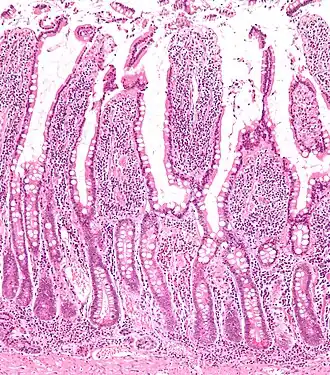

Microscopische vergroting die de darmvlokken in het dunnedarmslijmvlies laat zien met de darmvlokken en crypten van Lieberkühn. | ||||

Darmvlokken[1] ofwel villi intestinales[1] (enkelvoud villus intestinalis) zijn de vlokkige aanhangsels in de darmen (vooral in de dunne darm). Er zijn villi en microvilli.

De darmwand van de dunne darm is geplooid. Deze darmplooien zorgen voor een enorme oppervlaktevergroting. Op de plooien bevinden zich talrijke uitstulpingen, de darmvlokken of villi, die op hun beurt het oppervlak nog meer vergroten. Het totale contactoppervlak van de dunne darm bedraagt uiteindelijk tussen 150 en 200m². Het contact met de verterende voedselmassa is daardoor optimaal. Door middel van resorptie worden voedingsstoffen hier via de epitheelcellen, waaruit de darmwand bestaat, in het bloed opgenomen. In de villi zitten reinigende lymfevaten en haarvaten. Het met voedingsstoffen verrijkte bloed uit de darmvlokken gaat vanuit de darm-haarvaten naar de poortader, die de voedingsstoffen naar de lever vervoert. In de lever neemt de stofwisseling een aanvang.